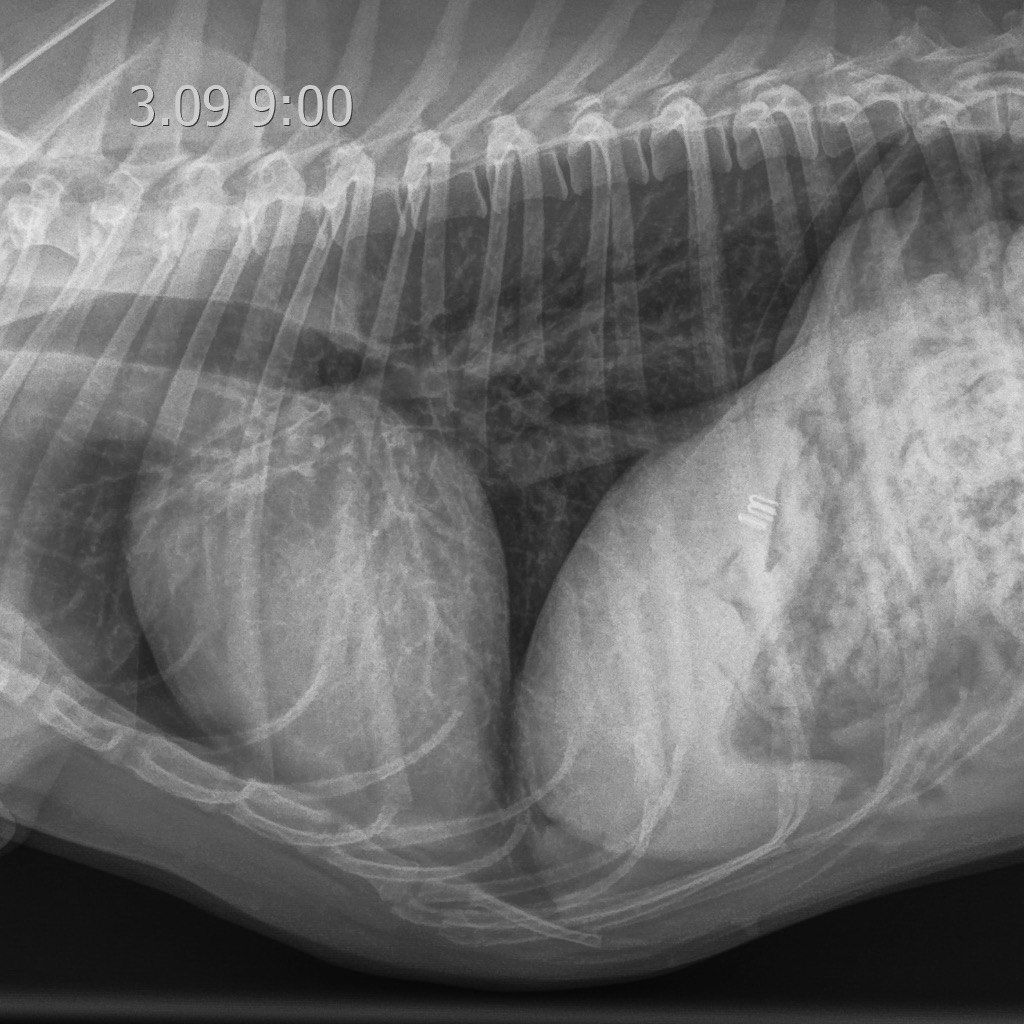

На восьмые сутки пребывания в ОРИТ у пациента наблюдались полное восстановление аппетита, нормализация общего состояния и активности. Респираторные симптомы были купированы, а рентгенологическая картина пришла в норму (рис. 11). Терапия включала использование доксициклина и спиронолактона в ранее установленных дозировках.

Синдром лептоспирозного легочного кровотечения (англ. leptospiral pulmonary haemorrhage syndrome; LPHS) является тяжелым проявлением острого лептоспироза и в последние годы все чаще диагностируется у собак и других видов животных14. Гистопатологические поражения легочной ткани при LPHS имеют схожие характеристики у разных видов и проявляются различной степенью внутриальвеолярного кровоизлияния при отсутствии выраженного воспалительного клеточного инфильтрата или васкулита. Внутриальвеолярный отек, фибрин и гиалиновые мембраны, характерные для патологий с диффузным альвеолярным повреждением (например, острый респираторный дистресс-синдром; ОРДС), также могут наблюдаться при LPHS, но не являются доминирующими признаками15. Патогенетические механизмы LPHS плохо изучены. В настоящее время исследуются несколько гипотез, включая системные воспалительные, иммуноопосредованные и прямые эффекты, вызываемые лептоспирами. Внутриальвеолярное кровоизлияние может быть обнаружено даже у собак без явных респираторных признаков17. Это указывает на то, что LPHS может быть более распространенным у собак с лептоспирозом, чем принято считать. Рентгенографические изменения, указывающие на LPHS, обычно первоначально проявляются в каудодорсальных отделах легочных полей и, как правило, носят двусторонний и недолевой характер. Поражения варьируются от легкого интерстициального рисунка до легкого или тяжелого ретикулонодулярного легочного рисунка с очаговыми альвеолярными инфильтратами. У некоторых собак наблюдается небольшое количество плеврального выпота (рис. 10). Рентгенографические изменения могут присутствовать даже при отсутствии клинических признаков респираторных нарушений26.